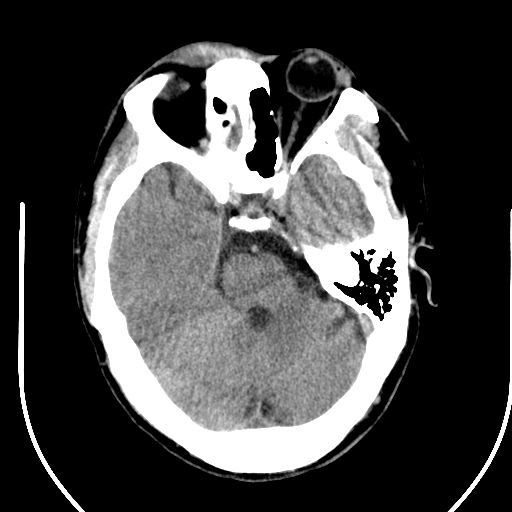

标题: CT25423:头部外伤意外发现右顶叶??? [打印本页]

标题: CT25423:头部外伤意外发现右顶叶???

ct值约13hu。

边缘清晰,没有占位效应,不像脑沟,结合ct值,软化灶可能吧

与脑沟没关系,小软化灶或陈旧性感染吧!

看样年纪不小了直接报腔梗,当然你要想报软化灶也是一样的

考虑右侧额叶巨腔隙灶;建议必要时行mri检查。